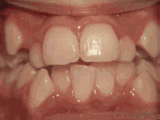

第九种

深覆盖,咬牙时,上牙差不多完全把下牙挡住了,经过矫正后的牙齿是这样的